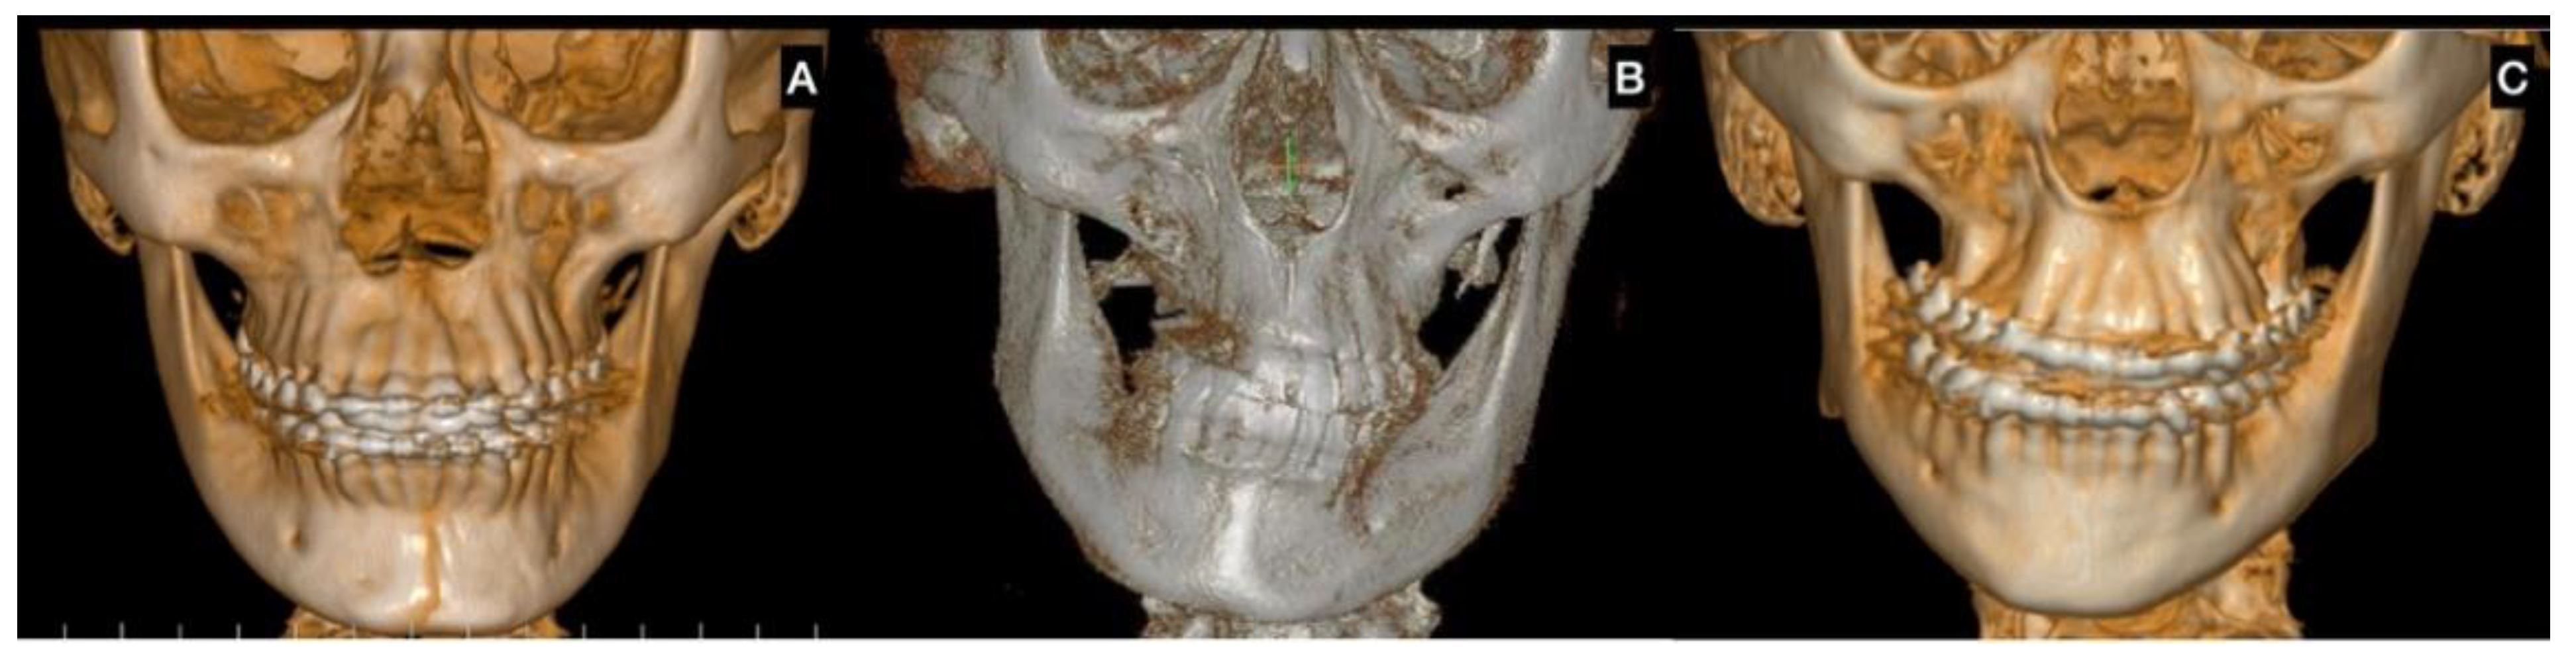

| CBCT | Augmentation in condylar size in comparison to the non-hyperplastic condyle |

| Lack in upper cortical line of the affected condyle in the upper area showing an active metabolism | |

| Augmentation in radiolucency in the affected condyle with an image related to poor density in some cases | |